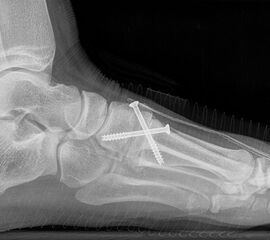

Röntgen

Standard ist die belastete Röntgenaufnahme des Fußes dorso-plantar und seitlich. Günstig ist eine Röhrenkippung von 10°-20°, um die Gelenke der Lisfranc-Linie einsehen zu können.

• medial aufklappende Cuneiforme I Osteotomie 1522

• Nach Schluss der Wachstumsfugen: TMT I Arthrodese nach Lapidus 2425